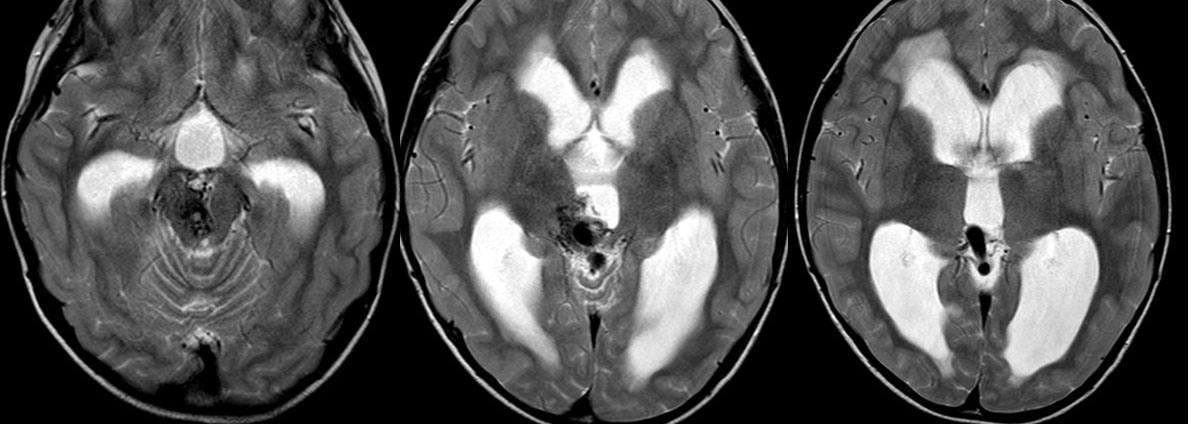

Thông động tĩnh mạch não

» Thông tin: Nam giới – 10 tuổi.

» Lâm sàng: Đau đầu.